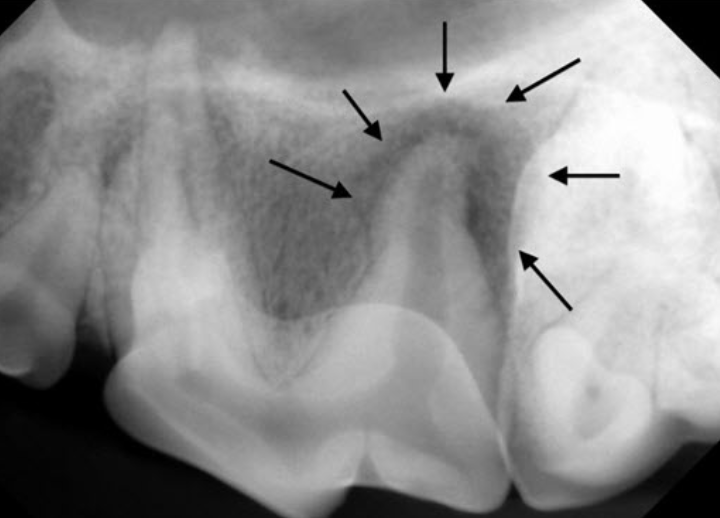

圖片來源:https://www.montanapetdental.com/periapical-lucencies/

動物牙科X光機使用時機3:牙髓(根管)疾病治療

許多動物在日常生活中常會去啃咬像骨頭、木頭、家具、較硬的玩具或球類等物品,這些行為都可能使牙齒受到過度磨損,甚至是斷裂,而牙髓裸露的情況就有機會隨之發生,需要進一步進行「牙髓(根管)疾病治療」。

全球小動物獸醫協會發布的準則顯示(註3),49.6 %的動物都有「牙齒折斷」的經驗,其中更有10%的狗狗發生過至少1顆以上的牙齒,有牙髓裸露的情況,而裸露後若造成牙髓感染發炎,很多時候光看表面是無法察覺異狀的!

以動物的習性而言,顯少表現出任何明顯的臨床症狀,所以在診斷或確定治療前,動物很可能早就飽受長時間的牙疼問題,故在外在表徵不太明顯的情況下,使用牙科X光機拍攝,即可直覺性地協助獸醫師經準判斷治療方式。